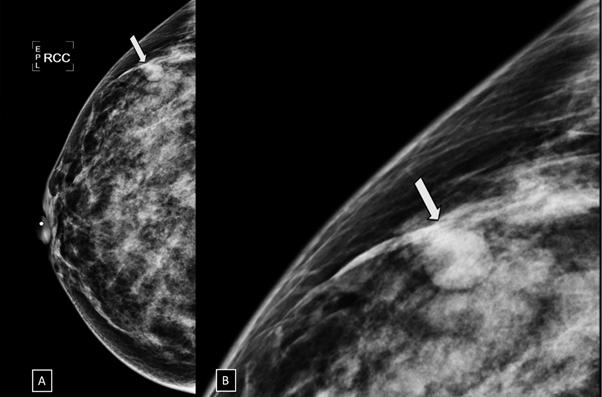

Figure 3 Digital breast tomosynthesis (DBT) in MLO projection. The margins of the nodule are well defined (white arrow) and the architectural distortion is confirmed (black arrow).

Figure 4 Digital breast tomosynthesis (DBT) in CC projection. The margins of the nodule are well defined (white arrow) and the architectural distortion is confirmed (black arrow).